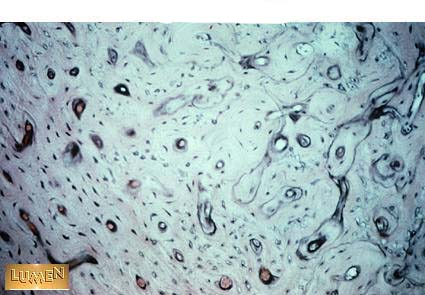

What kind of bone is this?

Compact